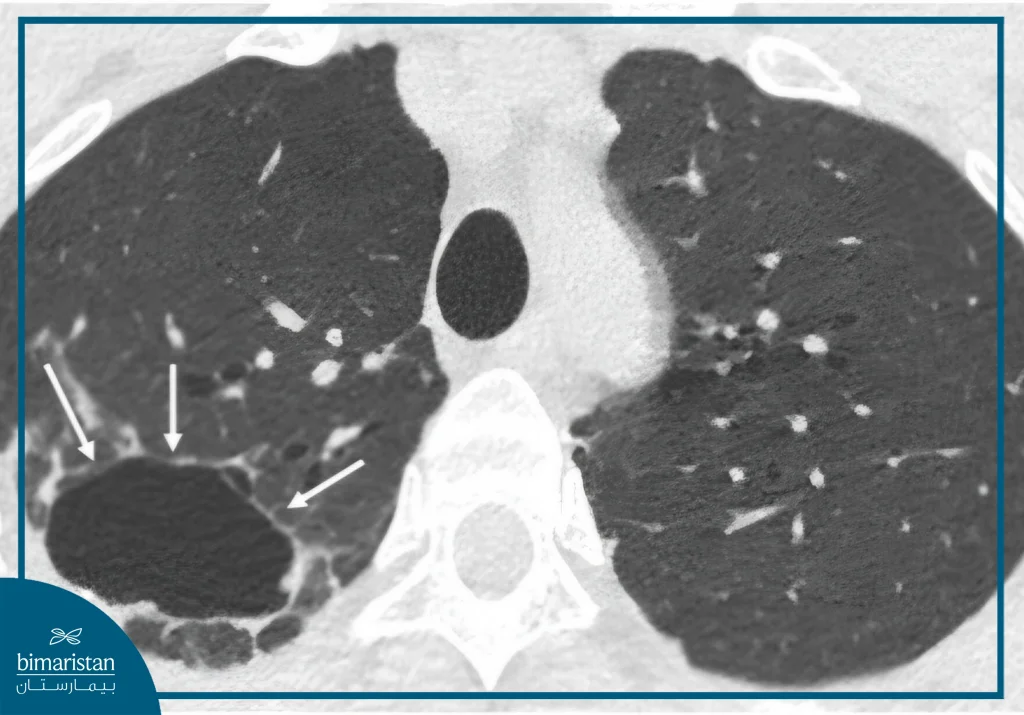

During an LDCT scan, the patient lies on a moving table and passes through a CT scanner that takes a series of images of the lungs with a low radiation dose compared to traditional scans. A computer then stitches the images together to form a detailed view that enables doctors to detect any very small nodules or tumors.

The patient is asked to lie on a flat table that slowly slides into the machine. During the scan, the table moves back and forth as the radiation tube rotates around the chest, sending tiny beams of radiation from different angles. The machine captures these beams and converts them into detailed cross-sectional images of the lungs that show even the smallest changes or nodules.

2. Detection of small pulmonary nodules

A small lung nodule (Lung Nodule) is a very common finding, detected in about half of the people who are screened. The majority of these nodules are noncancerous and may represent the remnants of old infections or simple fibrosis of lung tissue. In this case, no immediate action is taken, but it is recommended to re-examine after 3 to 12 months to monitor the size of the nodule and make sure it is stable.

3. Large pulmonary nodules or suspicious changes

When images reveal a large pulmonary nodule or a mass with characteristics suggestive of cancer (such as irregular edges or increased density), the patient is referred to a chest pathologist or oncologist for a detailed evaluation and diagnostic plan that includes biopsy or advanced testing. The earlier the detection, the higher the chances of successful treatment and complete tumor removal.